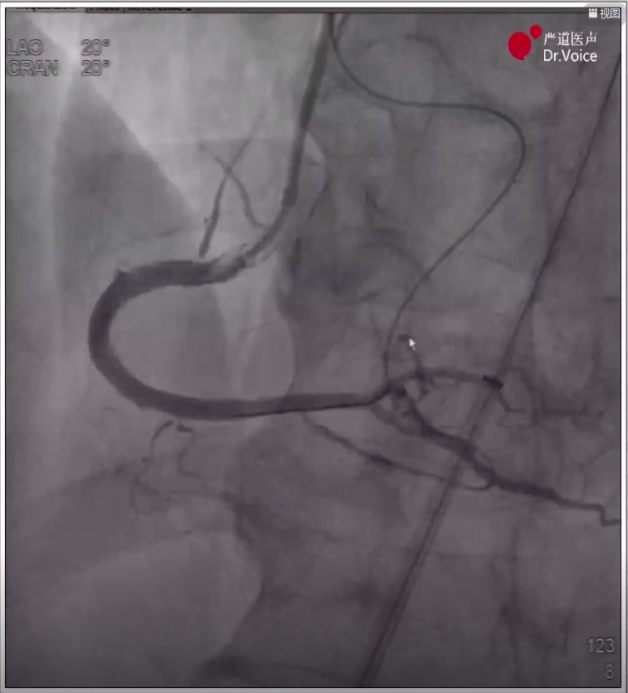

7、重新送入导管后,调整正向和逆向导丝重叠,通过AGT技术将逆向导丝送入正向指引导管,正向球囊锚定逆向导丝后,跟进逆向corsair150微导管至正向指引导管,正向runthrough导丝穿逆向微导管后完成轨道建立。

逆向导丝进入正向导管内

8、在IVUS指导下完成支架植入,最终造影显示血管恢复通畅,分支均保留,未见夹层及穿孔。

RCA远端残余狭窄

RCA最终造影效果